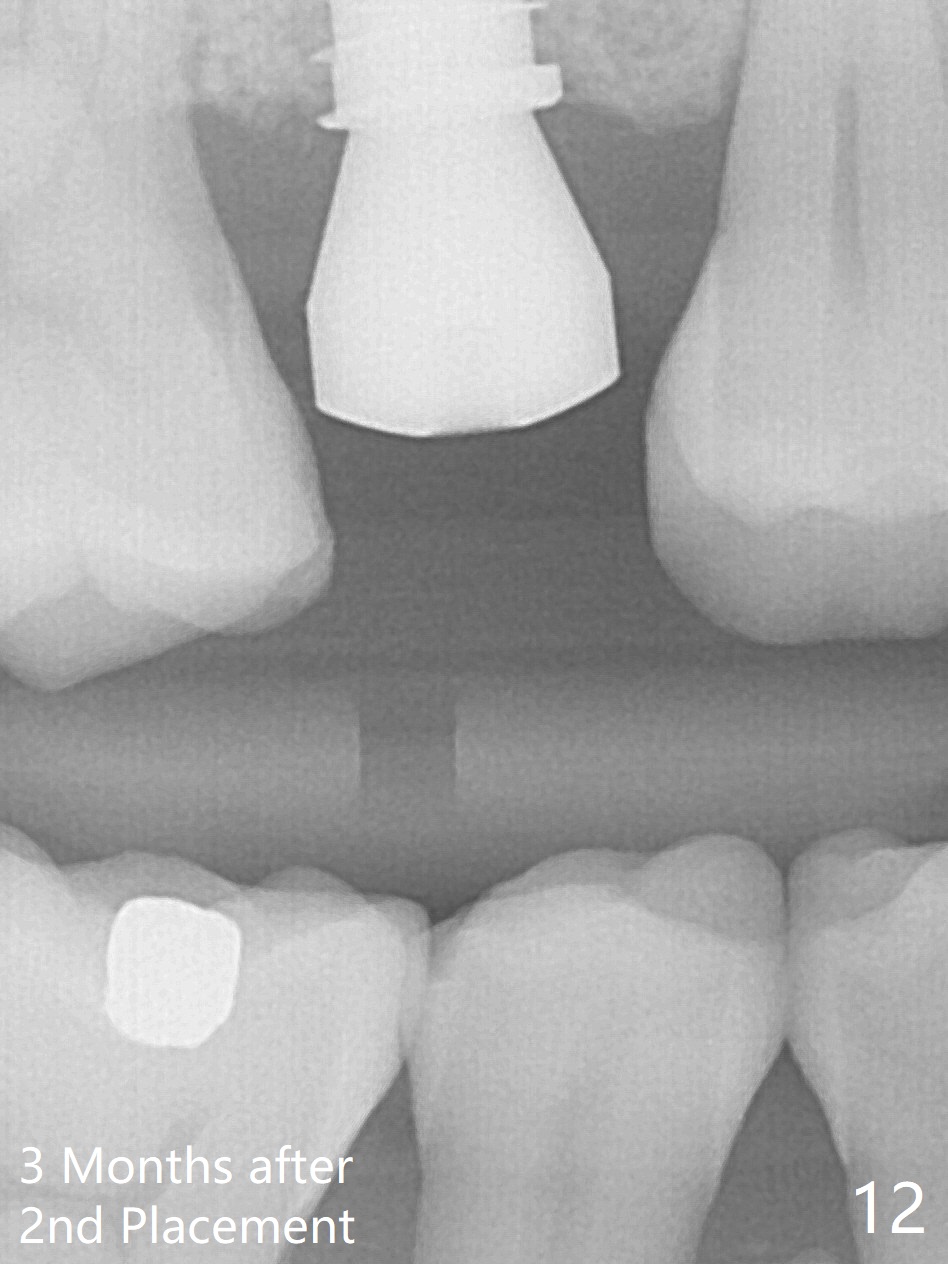

A 47-year-old man returns emergently with subgingival fracture of the lingual (L) cusp of the tooth #4 (Fig.1-3). After extraction (no bony defect) without drilling, a 4x11 mm dummy implant is placed as a tap drill with satisfactory stability (Fig.4,5). To get subcrestal placement, a shorter (4x9 mm) implant is inserted with insertion torque of < 35 Ncm. In retrospect, a larger implant (4.5 mm) would be better in term of primary stability. After allograft placement into the buccal and lingual gaps, a 4.5x4(4) mm abutment is placed for an immediate provisional. There is a peri-implant gap 7 months postop (Fig.7<, as compared to the implant at #2 (6 months postop)) . When the loose abutment is being retightened, the patient feels pain, although the gingiva appears healthy (Fig.8). A larger implant should have been used; the abutment should have been removed. The implant dislodges while the abutment is untightened 8 months postop. The osteotomy is found intact. A 4.5x11 mm dummy implant is placed 2 mm subgingival with 20 Ncm (Fig.9). When a 4.5x11 mm definitive implant is placed 3 mm subgingival (Fig.10,11), torque reaches 50 Ncm. A 5.5x3 mm healing abutment is placed. Three months postop, the implant is stable (Fig.12,13) and impression is taken.